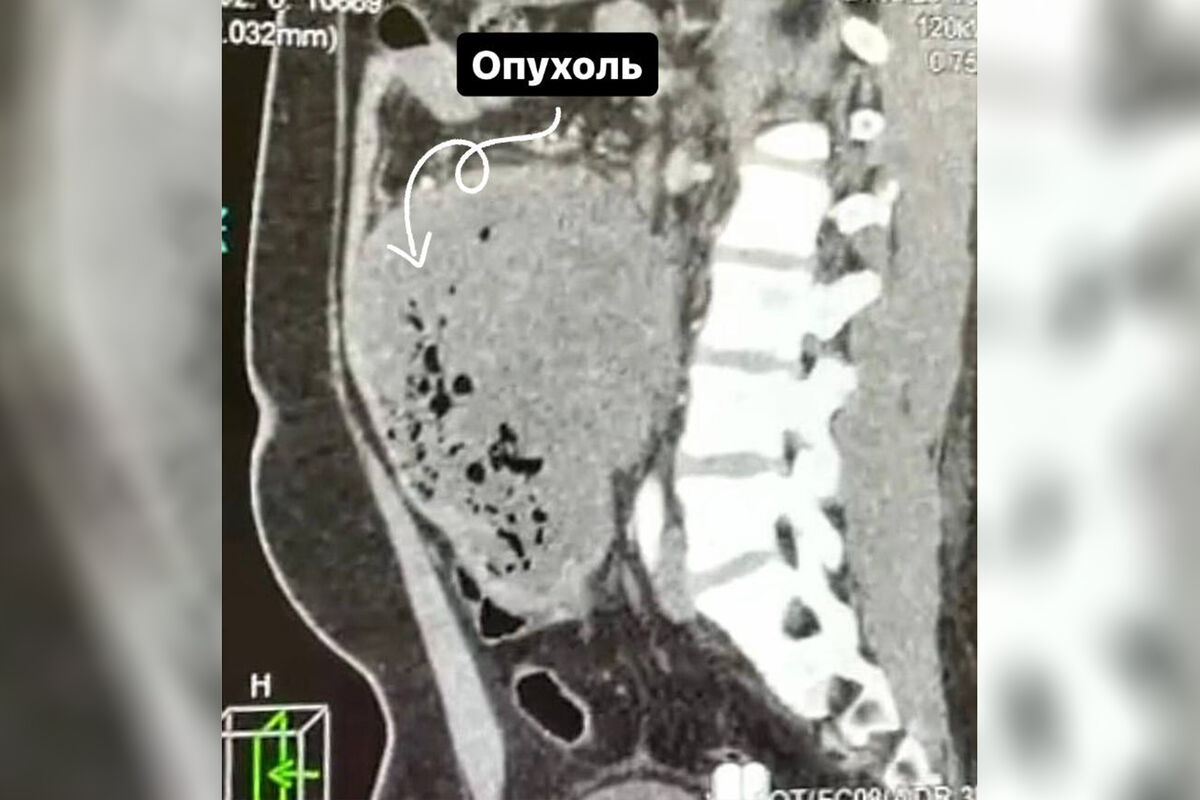

Врачи Долгопрудненской больницы прооперировали 21-летнего пациента со злокачественной опухолью размером 15 см, новообразование мужчина принял за кишечную инфекцию. Об этом сообщает минздрав Московской области.

«Ситуацию осложняла локализация опухоли, она находилась в труднодоступном для удаления месте — между аортой и нижней полой веной. Под общим наркозом мы удалили 15-сантиметровое образование вместе с участком кишки», — рассказал заведующий хирургическим отделением больницы Сергей Лисин.